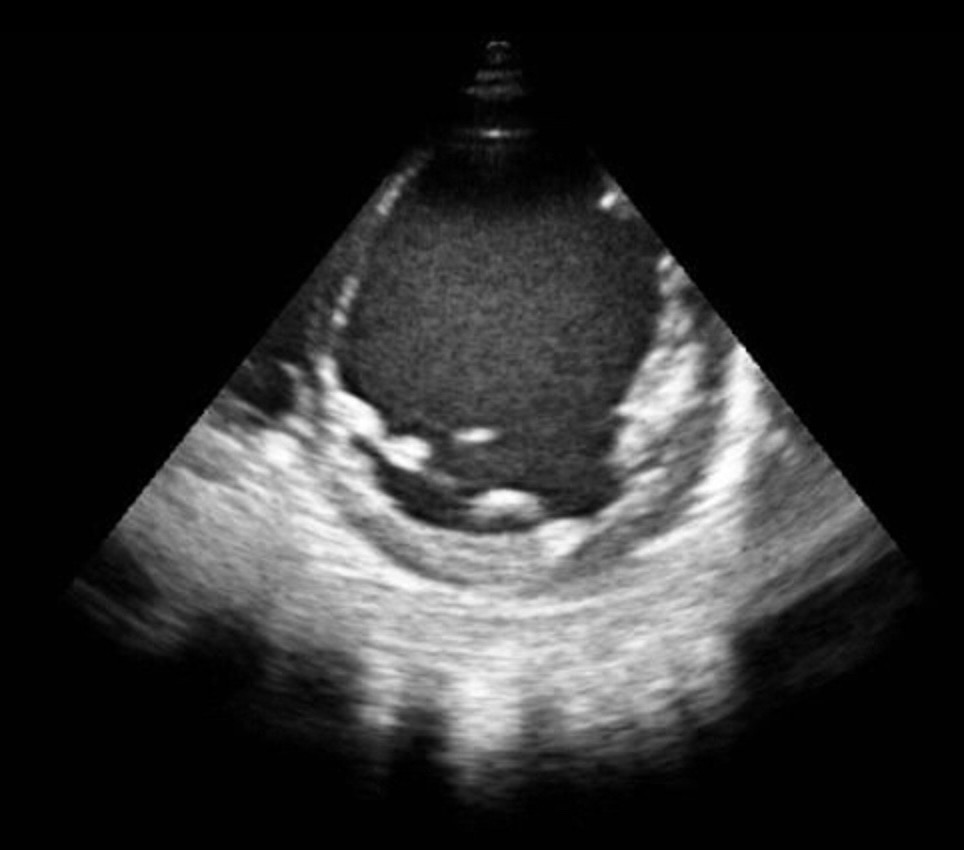

Eje corto y eje largo ecocardoscopia con dilatación severa ventrículo izquierdo, anillo mitral y aurícula izquierda, acinesia global ventrículo izquierdo, ausencia derrame pericárdico.